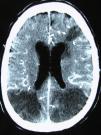

Hombre de 77 años que consulta por debilidad del brazo izquierdo y disartria. Refiere haber sido diagnosticado de hipertensión arterial y estar recibiendo enalapril/hidroclorotiazida, sin un control adecuado de su presión arterial. Ha sido fumador de 2 paquetes/día y sigue fumando en la actualidad. Ingresa en urgencias unos 90min después del comienzo de sus síntomas. No refiere cefalea, náuseas o vómitos. Su presión arterial es de 182/104mmHg con pulso irregular a 88 latidos por minuto. En la exploración neurológica se objetiva disartria, hemianopsia homónima izquierda, debilidad muscular e hipoestesia de miembros izquierdos. ¿Cómo debe ser evaluado y tratado este enfermo?

A 77-year old man who consulted due to left arm weakness and dysarthria. He reported having been diagnosed of high blood pressure and that he was taking enalapril/hydrochlorothiazide without adequate blood pressure control. He had smoked 2 packs of cigarettes a day and continues to smoke at present. He was admitted to the emergency service about 90min after the onset of his symptoms. He did not report headache, nausea or vomiting. His BP was 182/104mmHg, with irregular pulse at 88 beats per minute. The neurological examination revealed dysarthria, left homonymous hemianopsia, muscle weakness and hypoesthesia of the left limbs. How should this patient be evaluated and treated?